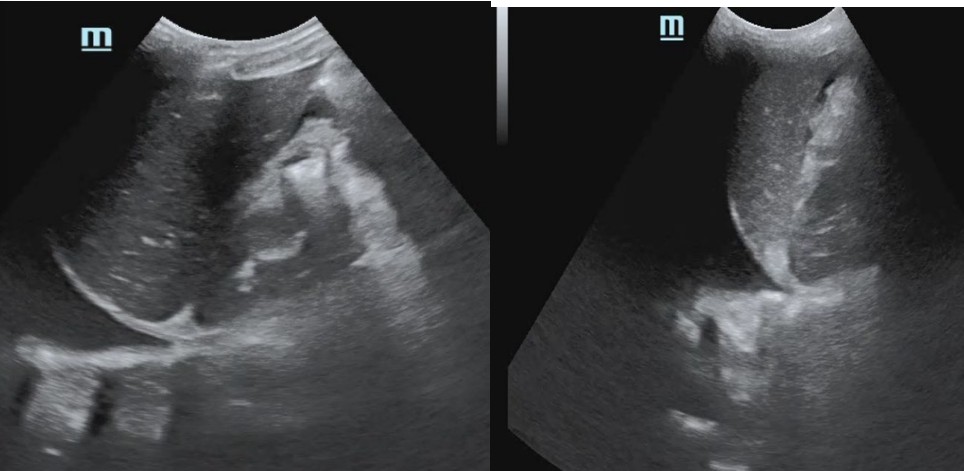

Early pregnancy bleeding

A 24-year-old woman presents with abdominal pain and vaginal bleeding. Her last menstrual period was eight weeks ago and pregnancy …